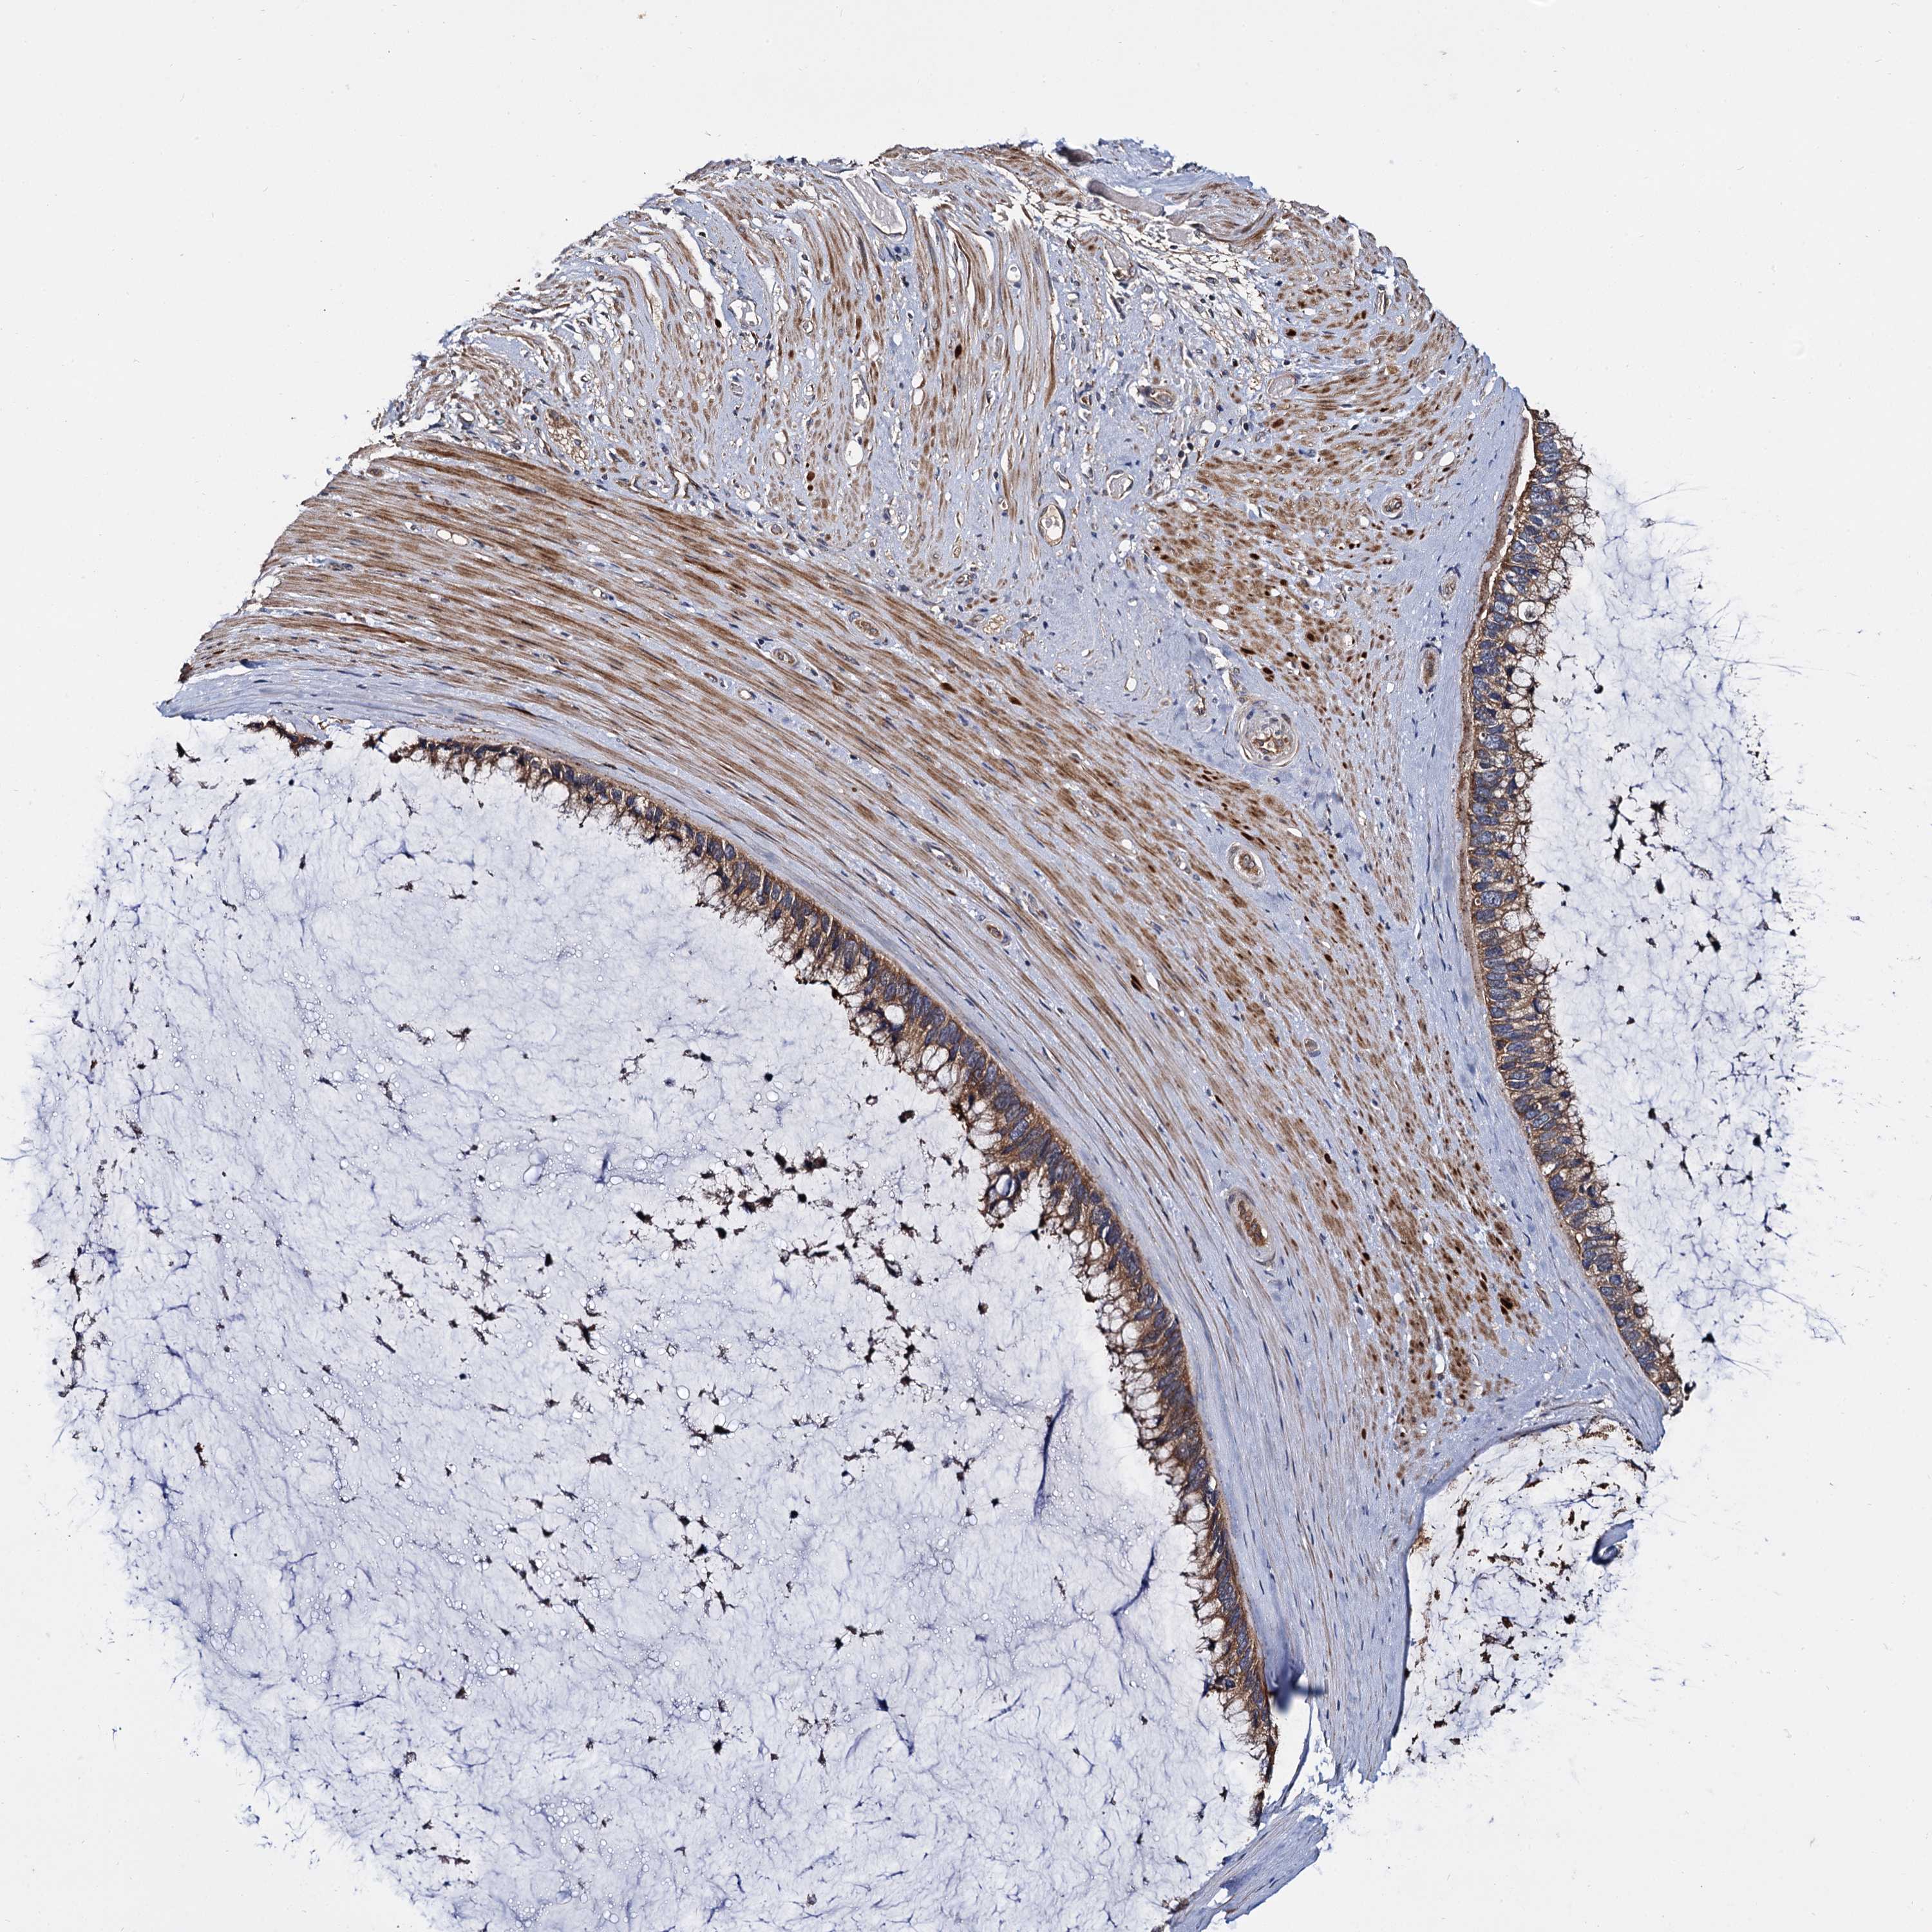

OVARIAN CANCER - Protein expressioni

A mouse-over function shows sample information and annotation data. Click on an image to view it in a full screen mode. Samples can be filtered based on level of antibody staining by selecting one or several of the following categories: high, medium, low and not detected. The assay and annotation is described here.

Note that samples used for immunohistochemistry by the Human Protein Atlas do not correspond to samples in the TCGA dataset.

Antibody stainingi

Antibody staining in the annotated cell types in the current human tissue is reported as not detected, low, medium, or high, based on conventional immunohistochemistry profiling in selected tissues. This score is based on the combination of the staining intensity and fraction of stained cells.

Each image is clickable and will lead to virtual microscopy that enables deeper exploration of all samples and also displays staining intensity scores, fraction scores and subcellular localization as well as patient and tissue information for each sample.

Antibody HPA039392

Antibody HPA040503

Cystadenocarcinoma, serous, NOS

Carcinoma, endometroid

Cystadenocarcinoma, mucinous, NOS

Carcinoma, NOS